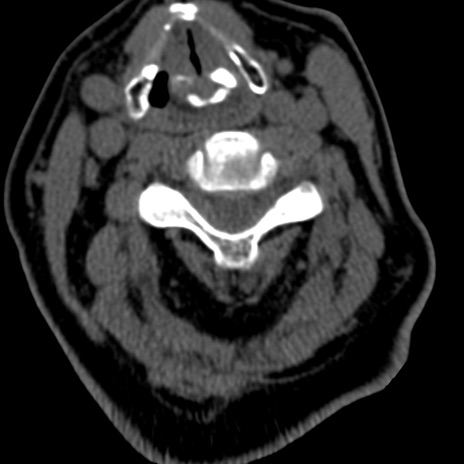

症例50 頚椎CT(横断像)

【症例】60歳代女性

【主訴】後頭部〜右後頸部にかけての痛み

【現病歴】本日飲食店でコーヒーを飲んでいたところ、突然後頭部〜右後頸部にかけて痛みが出現し、右上肢の感覚障害を伴ったため救急要請。

【身体所見】脳神経学的に明らかな異常所見を認めず。右上肢に軽度の感覚障害あり。

異常所見と診断は?

頚椎CT